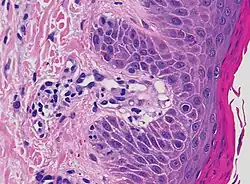

Main conditions[2] Characteristics Micrograph Photograph

Generally/Not otherwise specified Typical findings:[2]

• In the papillary dermis: a confluent, band-like, dense inflammation of mainly small lymphocytes and a few histiocytes, along or hugging the dermoepidermal junction.

• Often vacuolar degeneration of basal keratinocytes and apoptotic bodies (colloid or Civatte bodies).

Lichen planus Irregular epidermal hyperplasia with a jagged “sawtooth” appearance, compact hyperkeratosis or orthokeratosis, foci of wedge-shaped hypergranulosis, basilar vacuolar degeneration, slight spongiosis in the spinous layer, and squamatization. The dermal papillae between the elongated rete ridges are frequently dome shaped. Necrotic keratinocytes can be observed in the basal layer of the epidermis and at the dermal-epidermal junction. Eosinophilic remnants of anucleate apoptotic basal cells may also be found in the dermis and are referred to as “colloid or civatte bodies”. Whickham striae are usually seen in the areas of hypergranulosis. Vacuolar degeneration at the basal layer may be noted leading to focal subepidermal clefts (Max Joseph spaces). Squamatization occurs as a result of maturation and flattening of cells in the basal layer. It happens in areas of marked hypergranulosis with prominence of the sawtooth pattern of rete ridges. Wedge-shaped hypergranulosis can occur in the eccrine ducts (acrosyringia) or hair follicles (acrotrichia). In the hypertrophic subtype, the associated hyperkeratosis, parakeratosis, hypergranulosis, papillomatosis, acanthosis, and hyperplasia markedly increased with thicker collagen bundles forming in the dermis. Moreover, the rete ridges are more elongated and rounded as opposed to the typical sawtooth pattern. In atrophic LP, loss of the rete ridges and dermal fibrosis is prominent. In vesiculobullous LP, the disease progression is quicker. Hence, some of the distinctive features such as hyperkeratosis, hypergranulosis, or dense lymphocytic dermal-epidermal infiltrate may not be present. LP lesion may resolve with residual hyperpigmentation caused by a persistent increase in the number of melanophages in the papillary dermis.[9]